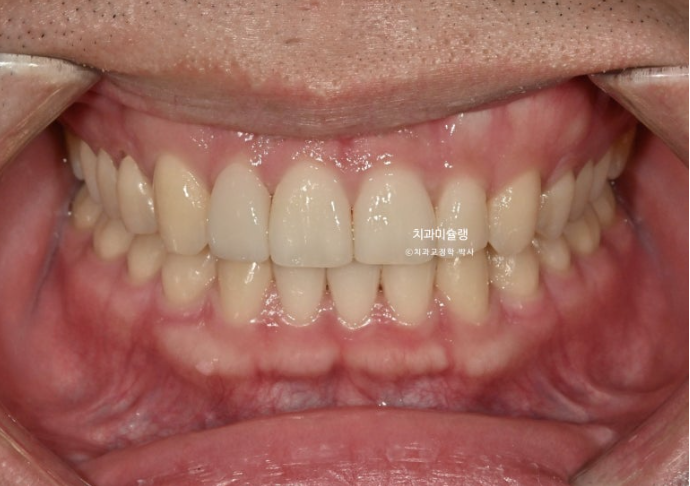

25.10~25.11

차례대로 교정 완료 직후 - 무삭제 라미네이트 부착 후 - 앞니 끝단 레진 치료 후 사진 입니다.

25년 11월 라미네이트 레진 등 보철을 포함한 모든 치료를 마무리 했습니다.

25.11